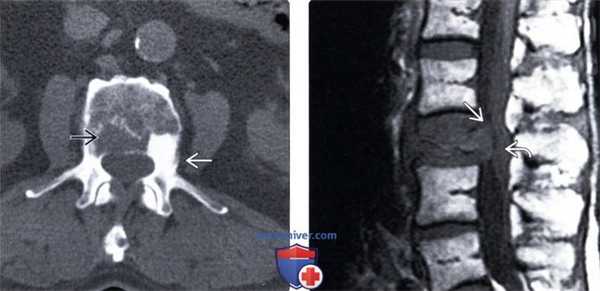

(Слева) При рентгенографии в боковой проекции отмечается остеолиз дуги С2 и верхнею края дуги С3.

(Справа) Сагиттальный срез, Т1-ВИ: у этого же пациента определяется массивное мягкотканное образование на месте дуги С2. Также отмечается замещение костного мозга тела и зубовидного отростка С2. В ходе последующего исследования у пациента выявлена мелкоклеточная карцинома в верхней доле правою легкою. (Слева) Аксиальный КТ-срез: массивный метастаз рака щитовидной железы в теле и левой половине дуги СЗ. Образование частично окружено тонким ободком увеличенной в объеме кости. Экстраоссальный мягкотканный компонент виден нечеткой.

(Справа) Аксиальный срез, КТ с КУ: накопление контраста В, типичное для гиперваскуляризированных опухолей, представителем которых является в т. ч. рак щитовидной железы. Внутренний край образования расположен в спинномозговом канале, деформирует дуральный мешок и скорее всего контактирует с шейным отделом спинного мозга.

(Слева) Аксиальный КТ-срез: определяется массивное остеолитическое образование, представляющее собой метастаз почечноклеточной карциномы и разрушающее правую заднюю половину тела Т7, распространяющееся на задние элементы и задний отрезок седьмого ребра.

(Справа) Данное аксиальное Т1-ВИ этого же пациента позволяет более точно оценить распространение процесса, поражающего ребра и правую половину тела Т7. Эпидуральный компонент опухоли на данном скане выражен минимально.

(Слева) Аксиальный КТ-срез: у пациента с метастазами рака предстательной железы отмечается смешанный литический и бластический характер метастатического поражения. Экстра -оссальное распространение опухоли на данном срезе оценить невозможно, кортикальные стенки позвонка выглядят неповрежденными.

(Справа) Сагиттальный срез, Т1-ВИ: коллапс тела L3 позвонка с диффузным снижением интенсивности сигнала вследствие метастатического поражения. Задняя покровная пластинка деформирована и выстоит в спинномозговой канал, вы зывая выраженное сдавление корешков конского хвоста, передний паравертебральный мягкотканный компонент отражает инфильтративный рост опухоли.